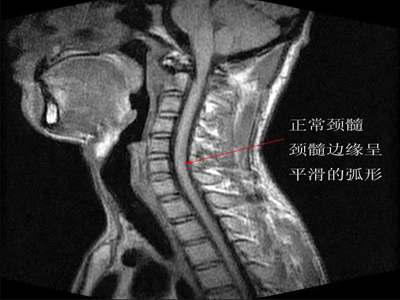

颈椎病易伪装成什么疾病症状?_病因病理_颈椎